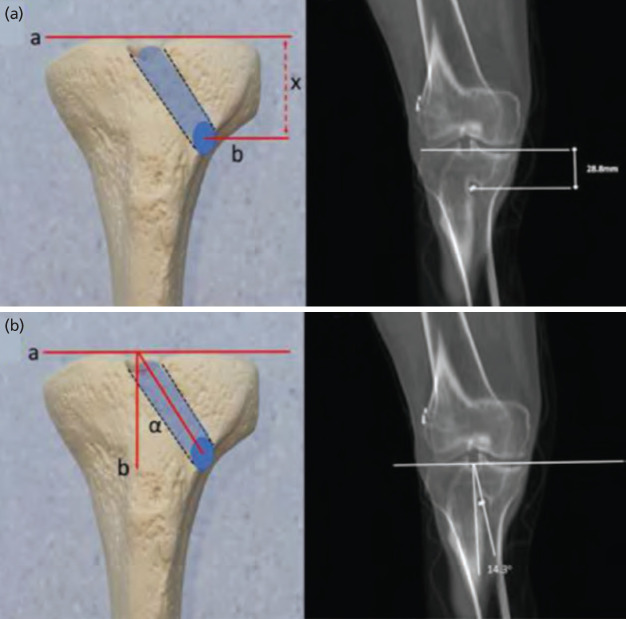

Introduction: Anterior cruciate ligament (ACL) reconstruction is a commonly performed surgical procedure. The objectives of this retrospective comparative study are (1) to evaluate the obliquity, size and the intra-articular aperture shape of the tibial tunnel in patients operated with an anteromedial portal technique, and (2) to determine their possible relation with revision surgery.

Material and methods: Patients operated for a primary ACL reconstruction between 2014 and 2018 were eligible. All patients of primary and revision ACL fulfilling the inclusion criteria were assessed for presence of a knee CT scan within one month of surgery and at least three years of follow-up. Several radiological parameters were measured for the study, among which: Tunnel height, Coronal tunnel angle, Maximal tunnel width and Sagittal tunnel inclination. Multivariate analyses were performed to identify parameters correlated with revision.

Results: Mean age of the primary group was 30.5±8.4 versus 29.4±8.0 of the revision group. The majority of patients were males in both groups (n=33, 76.7% and n=38, 95.0%, respectively). A longer diameter of the intra-articular ellipse (p=0.005) and an increased mid-tunnel to TT distance on the axial plane (p=0.006) were significantly correlated with revision. A ROC curve analysis determined a cut-off value of 27.9mm from the tubercle was an optimal entry point.

Conclusion: A greater distance between the mid-point of the tibial tunnel entrance and the centre of the tibial tubercle is linked to a higher risk of revision. An elongated elliptic shape in the antero-posterior plane also correlates with revision risk.